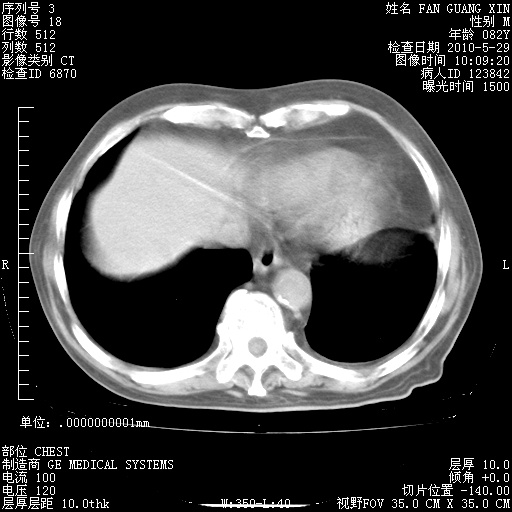

再治疗10天后的肺部CT

再治疗10天后的肺部CT 纵膈窗

阅读此次胸部CT,肺间质渗出性改变较入院时有吸收。目前从体温、白细胞、中性分叶明显增高,肯定存在细菌感染(发生医院感染哦,若无消化道及泌尿系统等感染的依据,肺部感染可能大)。若你院头孢哌酮舒巴坦钠耐药率较高,同意你的方案,若48小时体温仍高,可考虑使用碳青霉稀类抗菌药物,同时可予超声雾化、注意滴数时加大液体量。白蛋白33.30g/L较低哦,需加强营养等支持治疗。